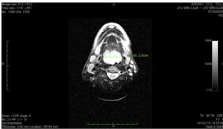

Inspection of the oral cavity revealed a large mass lesion. In the fiber optic endoscopic examination such lesion severely limited the oropharyngeal lumen (Figure 1). MRI scan showed lymphadenopathies in the jugular and submandibular regions, bilaterally. Furthermore, it revealed a remarkable thickening of the pharynx at the level of the lingual tonsil which caused a considerable limitation of pharyngeal lumen at the supraglottic level (4cm x 3.8cm x 2.46cm) (Figures 2 & 3). A total body positron emission tomography (PET) was performed as part of the staging work-up and there were no other lesions. The laterocervical lymphadenopathy was excised with no complicances. Histological analysis demonstrated a subverted lymph nodal architecture, irregular nuclei and a nodular/mantle growth pattern (Figure 4). Immunohistochemical phenotype was CD20+, CD5+, Cyclin D+, Bcl2+, CD23-, CD10-, Bcl6-, growth fraction (Ki67) ≈20%. The patient was treated with chemotherapy which consisted of three courses of Bendamustin-Rituximab every 28days for 6months followed by 2years of maintenance therapy. After chemotherapy, the lesion was completely disappeared.

Figure 4 Histological analysis showing atypical lymphoid cell proliferation, irregular nuclei and nodular/mantle growth pattern.